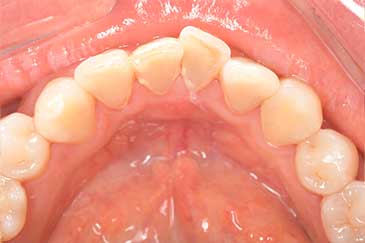

CASE 3

Before

After

基本情報

| 年齢・性別 | 30代・女性 |

|---|---|

| 主訴 | 定期検診 |

| 治療内容 | PMTC |

| 治療期間 | 60分 |

| 治療費 | 5,750円 |

| リスク・副作用 | しみる可能性があります。 |

| 治療方針 | PMTCでステインの除去。 |

| 担当者所見 | ステインが付きやすいため、3カ月毎の定期検診で除去する。 |